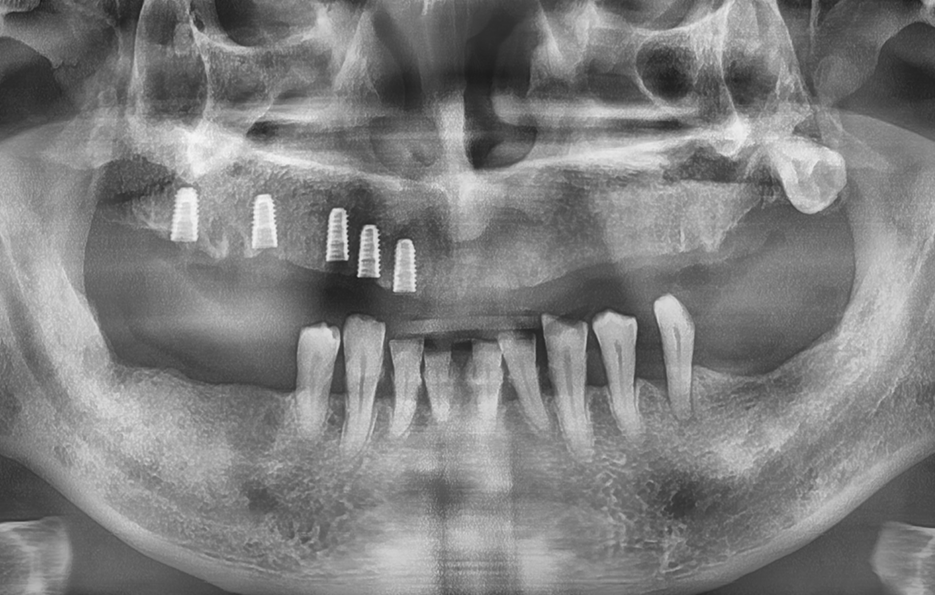

보통 윗니 전체 임플란트를 계획할 때 먼저 해야 하는 건 CT 촬영을 통한 잇몸 뼈 상태 진단으로 윗니는 아래보다 뼈가 더 얇고, 특히 어금니 쪽에는 상악동이라는 빈 공간이 있기 때문에, 임플란트를 심을 수 있는 잇몸 뼈의 양이 부족한 경우가 많다보니 이런 경우에는 단순히 임플란트를 심을 수 없기 때문에 상악동 거상술이라는 수술이 필요하게 되는 경우도 있는데요

이 수술은 상악동 점막을 들어 올리고 그 아래에 뼈이식 재료를 넣어서 임플란트가 들어갈 수 있는 충분한 공간을 만들어주는 방식이며 그 외에도 잇몸 뼈 상태나 전신 건강, 흡연 여부 같은 조건에 따라 구체적인 치료 방법이 달라지기 때문에 이처럼 윗니 전체 임플란트의 경우 기본적으로 임플란트를 지지할 수 있는 잇몸 뼈가 충분한지 정확한 진단이 치료의 시작점이 되고 있어요

전체 임플란트를 한다고 해서 꼭 치아의 상실 개수만큼 1:1로 임플란트를 심는 건 아니며 보통 무치악인 경우에는 6개에서 8개 정도의 임플란트를 일정한 간격으로 심고, 그 위에 여러 개의 치아가 연결된 브릿지 형태의 보철물을 올리는 방식으로 치료를 하며 환자의 경제적인 부분 부터 잇몸 뼈의 상태에 따라 임플란트의 식립 개수는 다소 차이가 있어요

예를 들어 잇몸 뼈가 충분히 있는 경우에는 임플란트를 더 많이 심어서 지지력을 높이고, 잇몸 뼈가 많이 줄어든 경우에는 임플란트의 식립 개수를 최소화 하는 방식으로 치료 방법이 달라지는 것이며 경우에 따라서는 임플란트 틀니 처럼 임플란트와 틀니의 중간 지점의 선택지를 활용하는 경우도 있어요